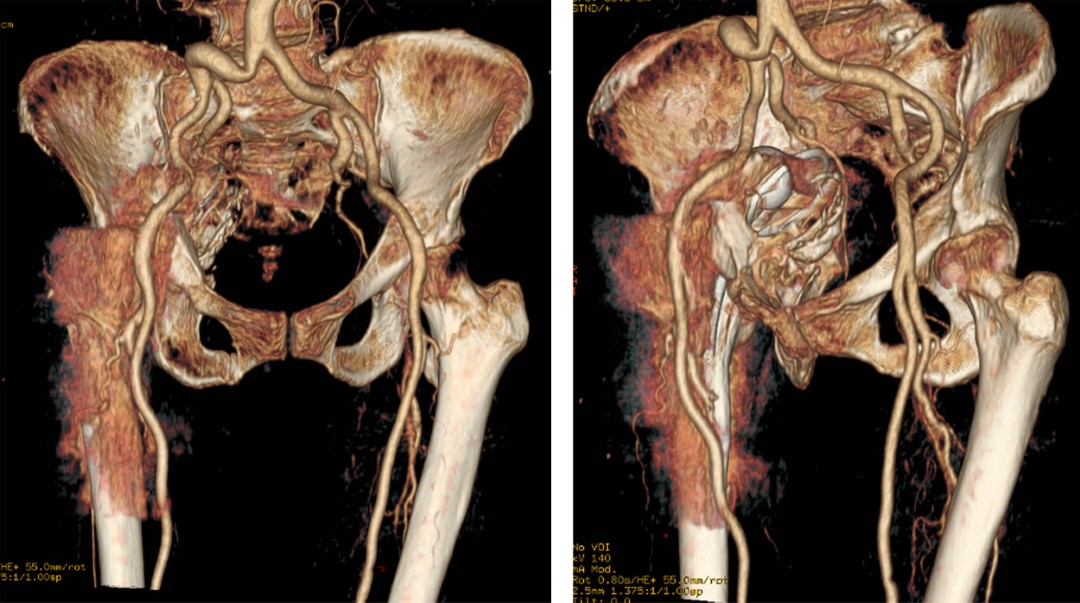

Con los hallazgos encontrados se solicitan estudios de imagen adicionales (Figuras 2 y 3).

Se diagnostica defecto acetabular óseo Paprosky4 IIIB + protrusión acetabular + fractura transversa de acetábulo + aflojamiento aséptico de vástago femoral en todas las zonas de Gruen a excepción de la zona 4 y 11. Por lo que se propone una cirugía de revisión protésica.

Posterior a las radiografías iniciales, es altamente recomendable solicitar una tomografía computarizada, ya que su reconstrucción tridimensional es altamente rentable para la planificación, el análisis de osteólisis pélvica y la discontinuidad pélvica. La resonancia magnética presenta limitaciones frente a la tomografía en esta patología específica.17,18,19,20,21

Cuando el componente acetabular ha migrado medialmente a la línea ilioisquiática es altamente recomendable solicitar una angiografía para descartar posibles complicaciones o patologías.

Figura 2

Figura 3